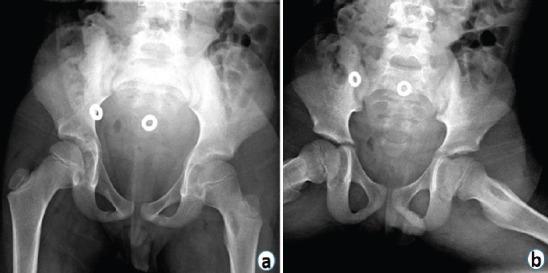

A 7-year-old male presented with complaints of hip pain and inability to bear weight. X-rays revealed Brodie's abscess in the proximal femur which was initially misdiagnosed as toxic synovitis with an incidental unicameral bone cyst (UBC).